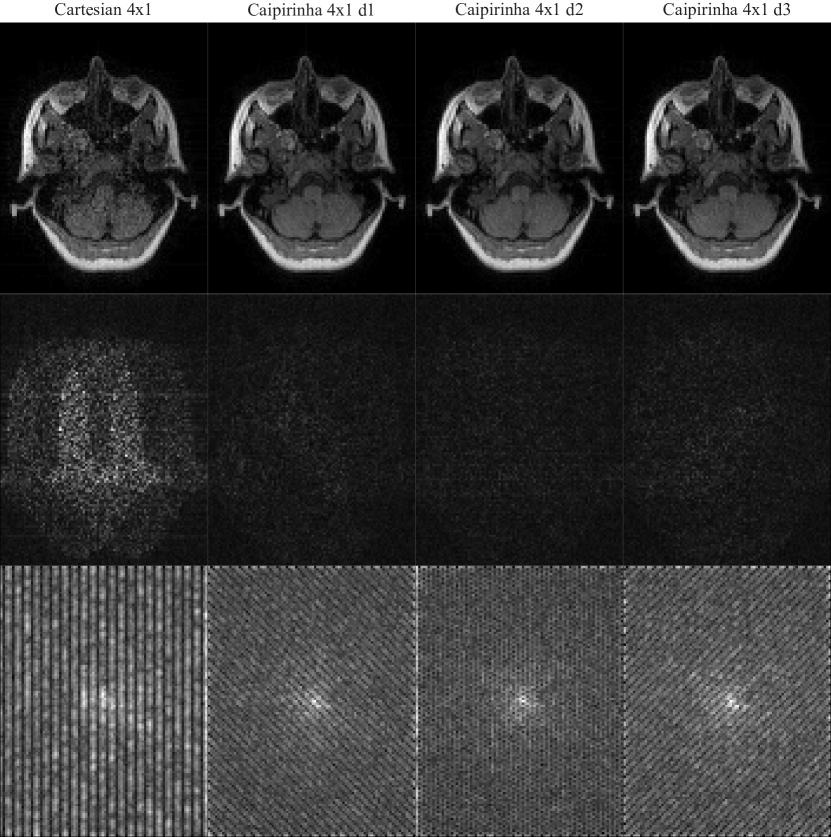

Refer to caption

Figure 6: Sampling pattern, combined power function, and local noise amplification for Cartesian 4×1414\times 1 and three different CAIPIRINHA sampling patterns with different shifts. Only a part of the full grid is shown.

Figure 7: Images reconstructed from noisy data (top) and corresponding error maps in the image domain (middle) and k-space domain (bottom) for Cartesian 4×1414\times 1 sampling and CAIPIRINHA with different shifts. The k-space maps have been raised to a power of 1/3131/3 for improved visualization.

The differences between Cartesian 4×1414\times 1 and the CAIPIRINHA patterns for the power function and Frobenius norm of the cardinal functions are shown in Figure 6. Essentially distributing the undersampling in both phase-encoding dimensions, all CAIPIRINHA patterns show much lower values for both functions than the Cartesian 4×1414\times 1 pattern. The CAIPIRINHA pattern with a shift of two performs slightly better with respect to noise amplification than the two others. The predictions are confirmed in the reconstructions from noisy data and corresponding error maps in image and k-space domain (Fig. 7).